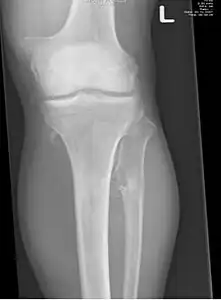

multiple osteochondromas around the knee